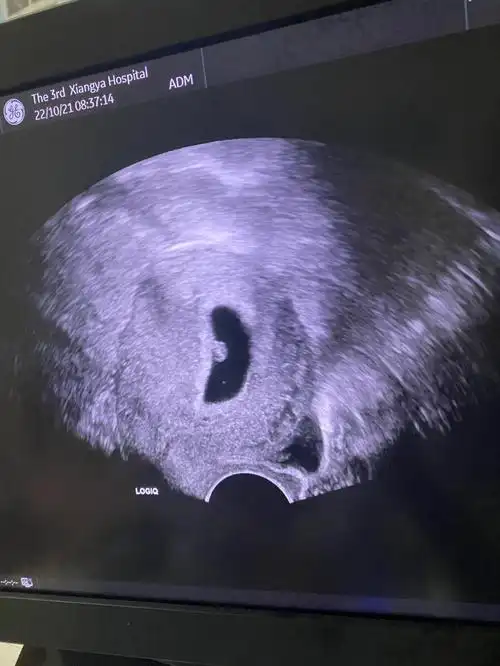

6周773可见胎心胎芽

9周终于见到胎心胎芽了(实际6周大小唉)

看到胎心胎芽

健康胎心胎芽